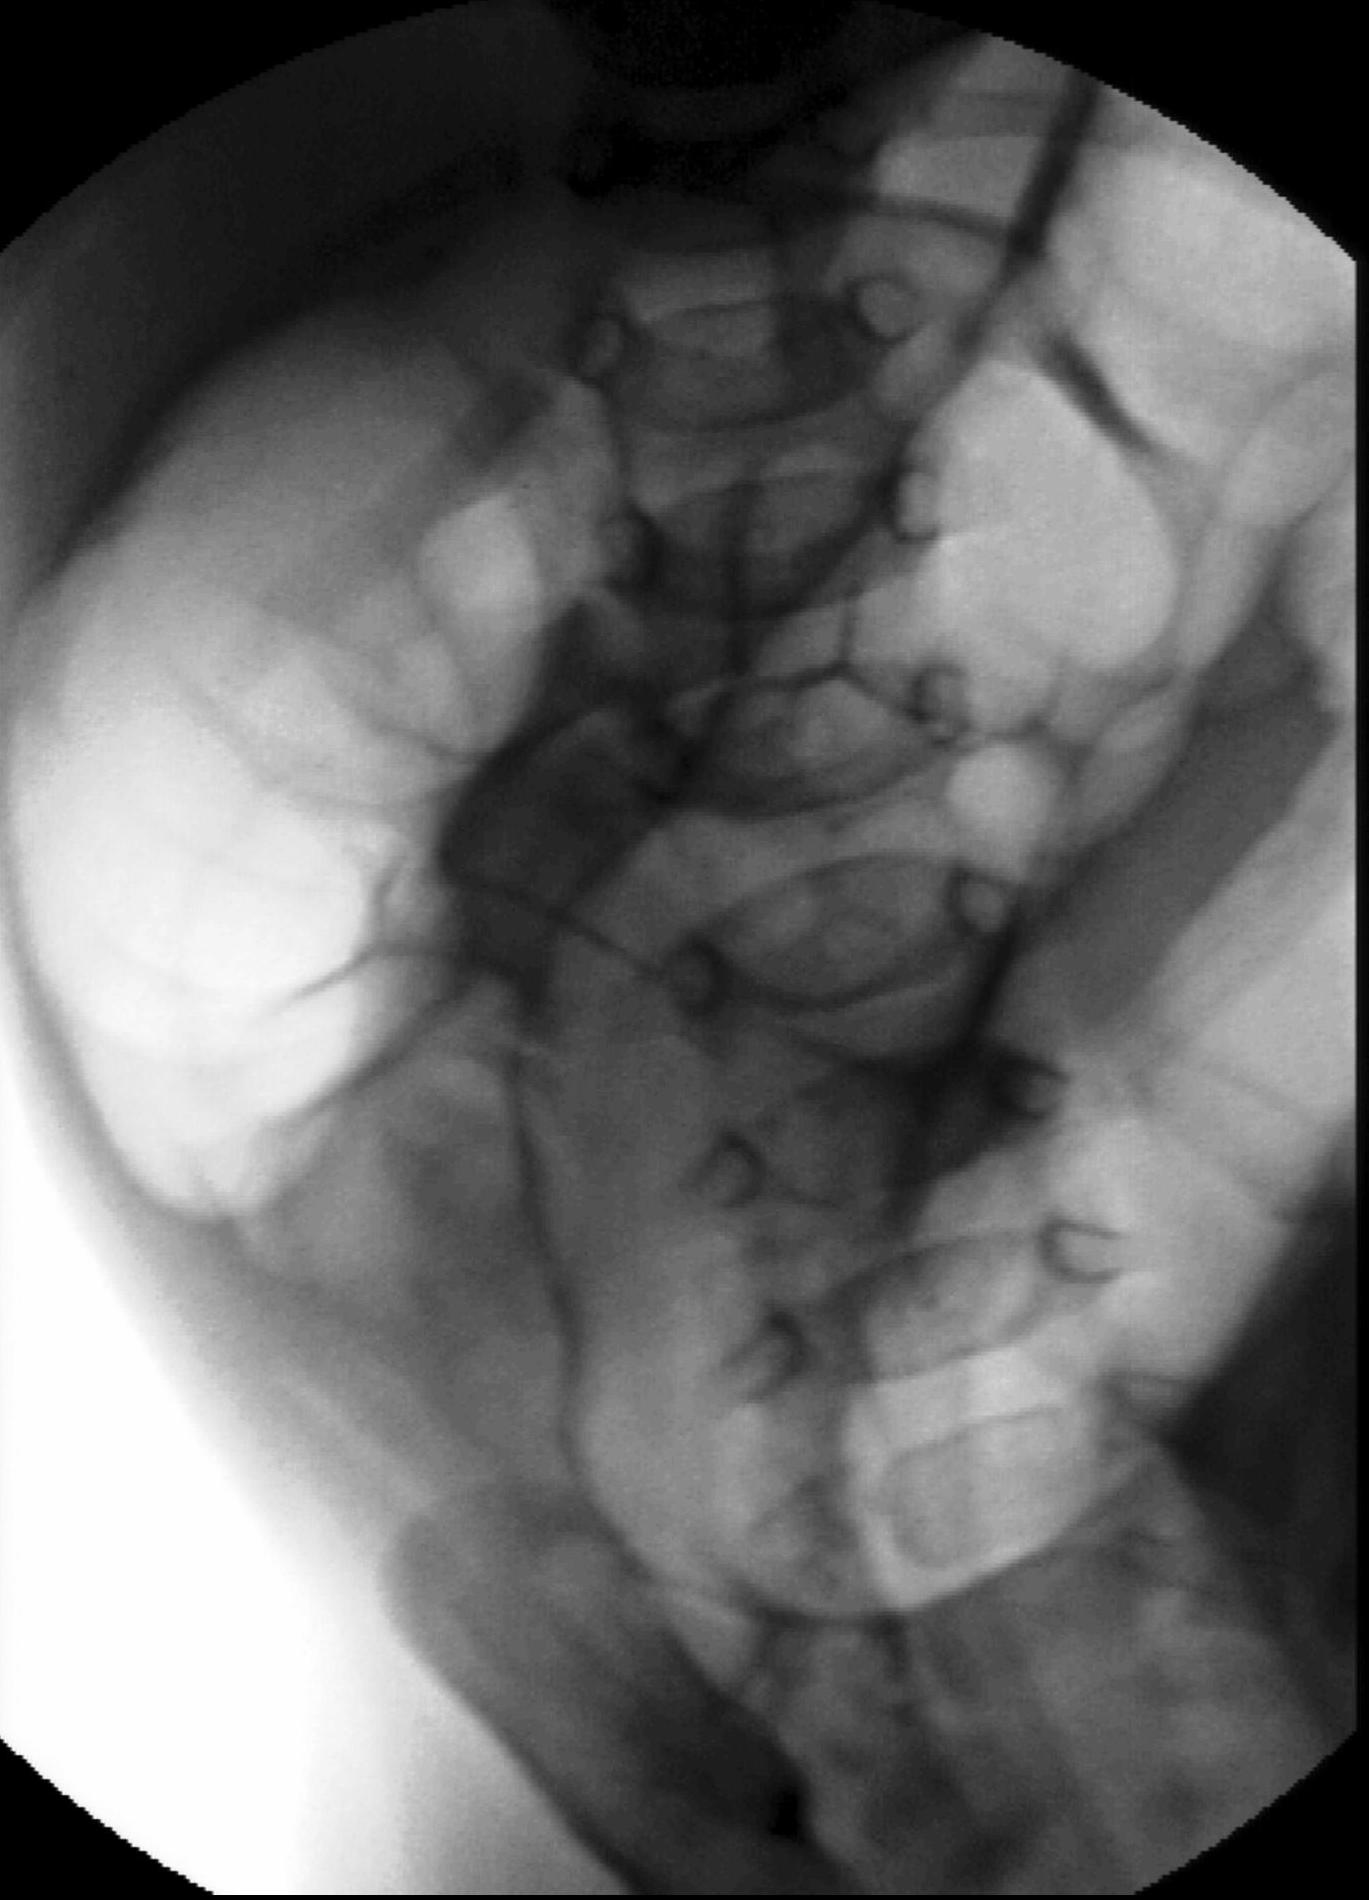

Vesicouretral (VU) reflux. Reflux stands for the reentry of urine from the bladder to the ureter and the collecting system of the kidneys due to the insufficiency of the uretrovesical valve. This can lead to a transient or a permanent dilatation of the urinary tracts. US can only raise suspicion for UV reflux through indirect signs such as thickened pyelon wall, small kidney, thinner and blurry cortico medullary junction, uneven parenchyma, thickened bladder wall. Reflux can be depicted with MCU or sonocystogrphy. Reflux is internationally categorized in 5 levels (I-V). Its special form is the intrarenal reflux that appears in the upper or lower pole of the kidney.

Miction cystourethrography. a. Reflux in the left normal diameter ureter.VUR l.s. Gr.I. b. Both ureters have a normal diameter as they refill with the contrast material refluxing from the bladder. VUR l.u. Gr.II. c. There is a slightly dilated right ureter and collecting system in the right kidney, the calices are widened. VUR l.s. Gr.III. d. Dilated ureter and collecting system can be seen on the left side. VUR l.s. Gr. IV. e. The right ureter is markedly dilated and elongated the pelvicalyceal system is also markedly dilated, the calices are rounded, contrast material appears in the tubules as well. VUR l.d. Gr.5. with intra-renal reflux.